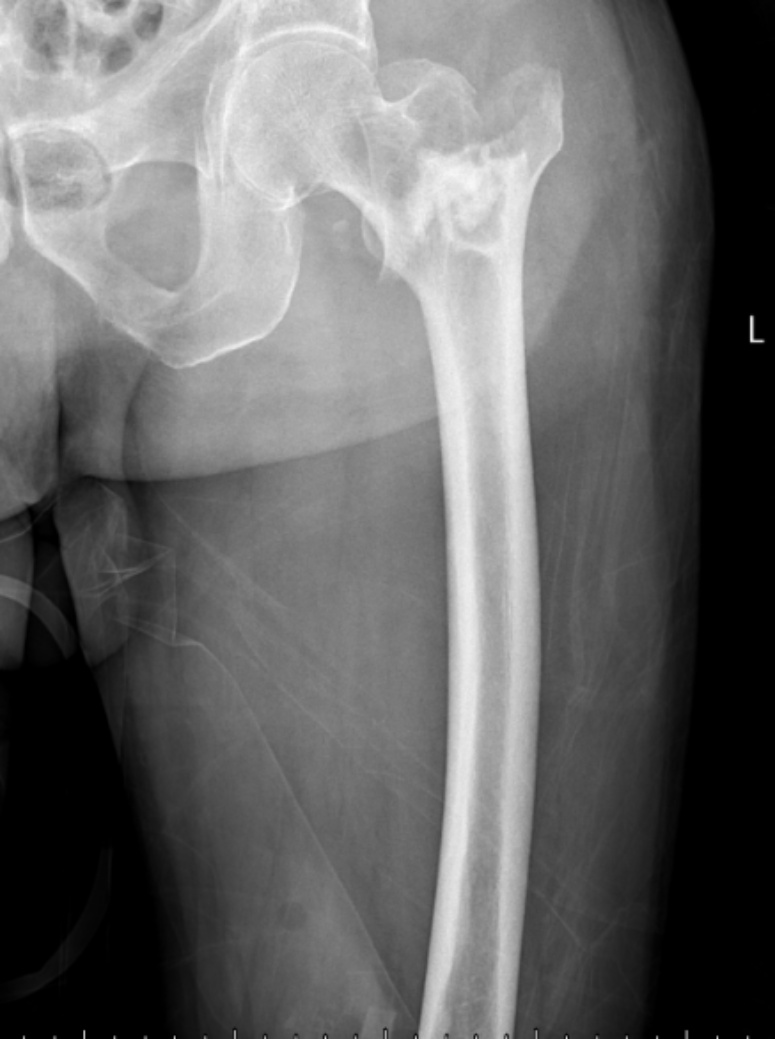

典型病例影像学表现见图1~10。图1为86岁女性右侧股骨转子间骨折(Evans Ⅲ型)患者,术前X线示骨折断端部分错位,术后X线示骨折位置可以及假体位置良好;图2显示了一名81岁男性患者,诊断为左侧股骨转子间骨折,类型为Evans V型,合并股骨干陈旧性骨折。患者接受了生物型加长柄半髋关节置换手术,并进行了股骨近端的钢丝捆扎内固定。术后X线示假体位置良好,股骨近端予钢丝捆扎固定;图3为87岁女性左侧股骨转子间骨折(Evans V型)患者,术后X线示假体位置良好,股骨大小转子骨折位置可,钢丝捆扎固定在位有效;图4为75岁女性左侧股骨转子间骨折(Evans V型)患者,术前X线示左侧股骨转子间骨折PFNA术后、骨折未愈合、内固定断裂。术后假体匹配良好,股骨近端钢丝内固定稳定可靠;图5为75岁男性左侧股骨转子间骨折(Evans IV型)患者,术后股骨大转子出现轻度位移,假体位置正常。图6为87岁男性左侧股骨转子间骨折(Evans V型)患者,给予DAA入路加长柄半髋关节置换,术前X线片,清晰地显示出左侧股骨转子间的骨折情况,术后X线影像,显示股骨的大小转子骨折位置良好,钢丝内固定装置在位稳定,假体位置良好;图7为77岁女性右侧股骨转子间骨折(Evans V型)患者,术前X线片显示右侧股骨转子间存在骨折且股骨大小转子均有累及和移位,术后X线片显示股骨小转子轻度移位,内固定装置位置稳定,假体位置良好;图8为70岁男性左侧股骨转子间骨折(Evans III型)患者,术前的X线片,清晰地显示了左侧股骨转子间的骨折情况,股骨近端髓腔钙化灶,术后假体位置满意;图9为77岁女性右侧股骨转子间骨折(Evans V型)患者,术前X线片,显示右侧股骨转子间及转子下部位骨折情况。术后假体匹配良好;图10为71岁男性右侧股骨颈骨折(Evans IV型)患者,术前X线片,显示右股骨转子间骨折的情况;术后X线表明股骨的大转子和小转子骨折位置保持良好,内固定装置稳固,术后假体位置正常。

Figure 9. A 77-year-old female patient with right intertrochanteric fracture of the femur (Evans V type). (a) Before surgery; (b) After surgery

9. 77岁女性右侧股骨转子间骨折(Evans V型)患者。(a) 术前;(b) 术后

(a) (b)